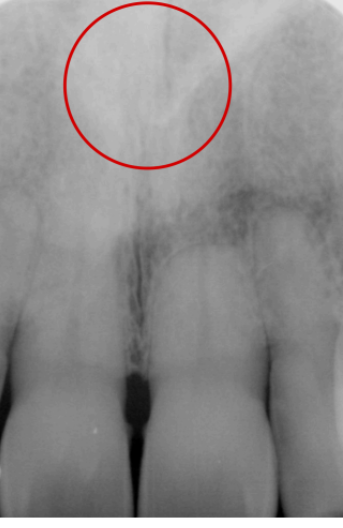

lateral fossa